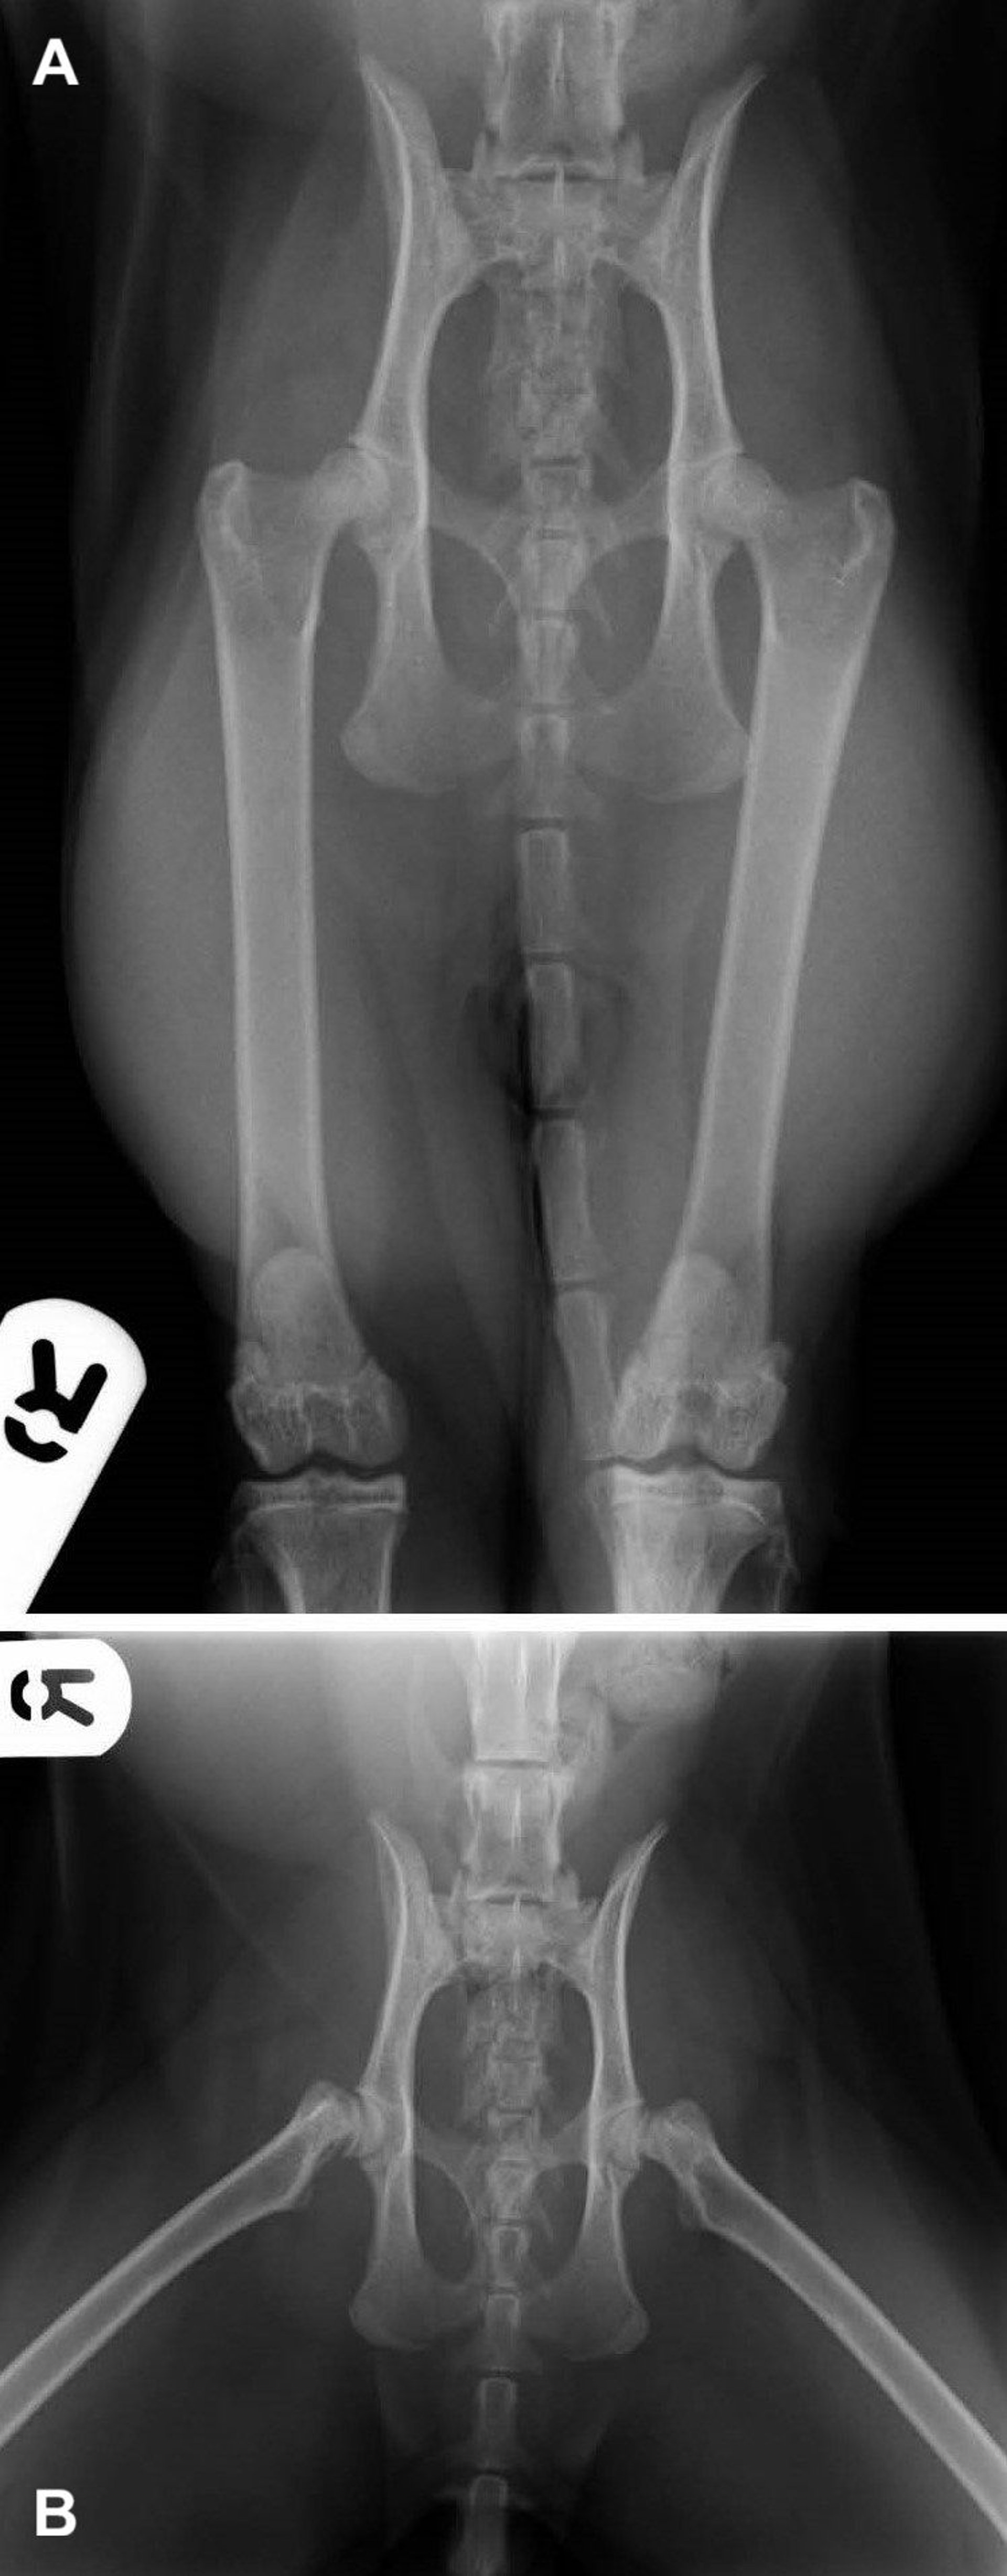

Cats, especially overweight, neutered males, frequently develop femoral capital physeal fractures (see feline capital physeal fracture images), often with minimal trauma, possibly because of delayed physeal closure.

Diagnosis of joint fractures relies on a combination of physical examination and diagnostic imaging. Standard radiographs are typically sufficient for identifying the fracture type and Salter-Harris classification (see canine capital physeal fracture image). In complex or articular fractures, CT scanning can offer additional detail for surgical planning.

Radiography is essential for confirming a diagnosis of hip luxation and for identifying any associated fractures or joint abnormalities that could influence treatment decisions (see hip luxation image). At least two orthogonal views are necessary.